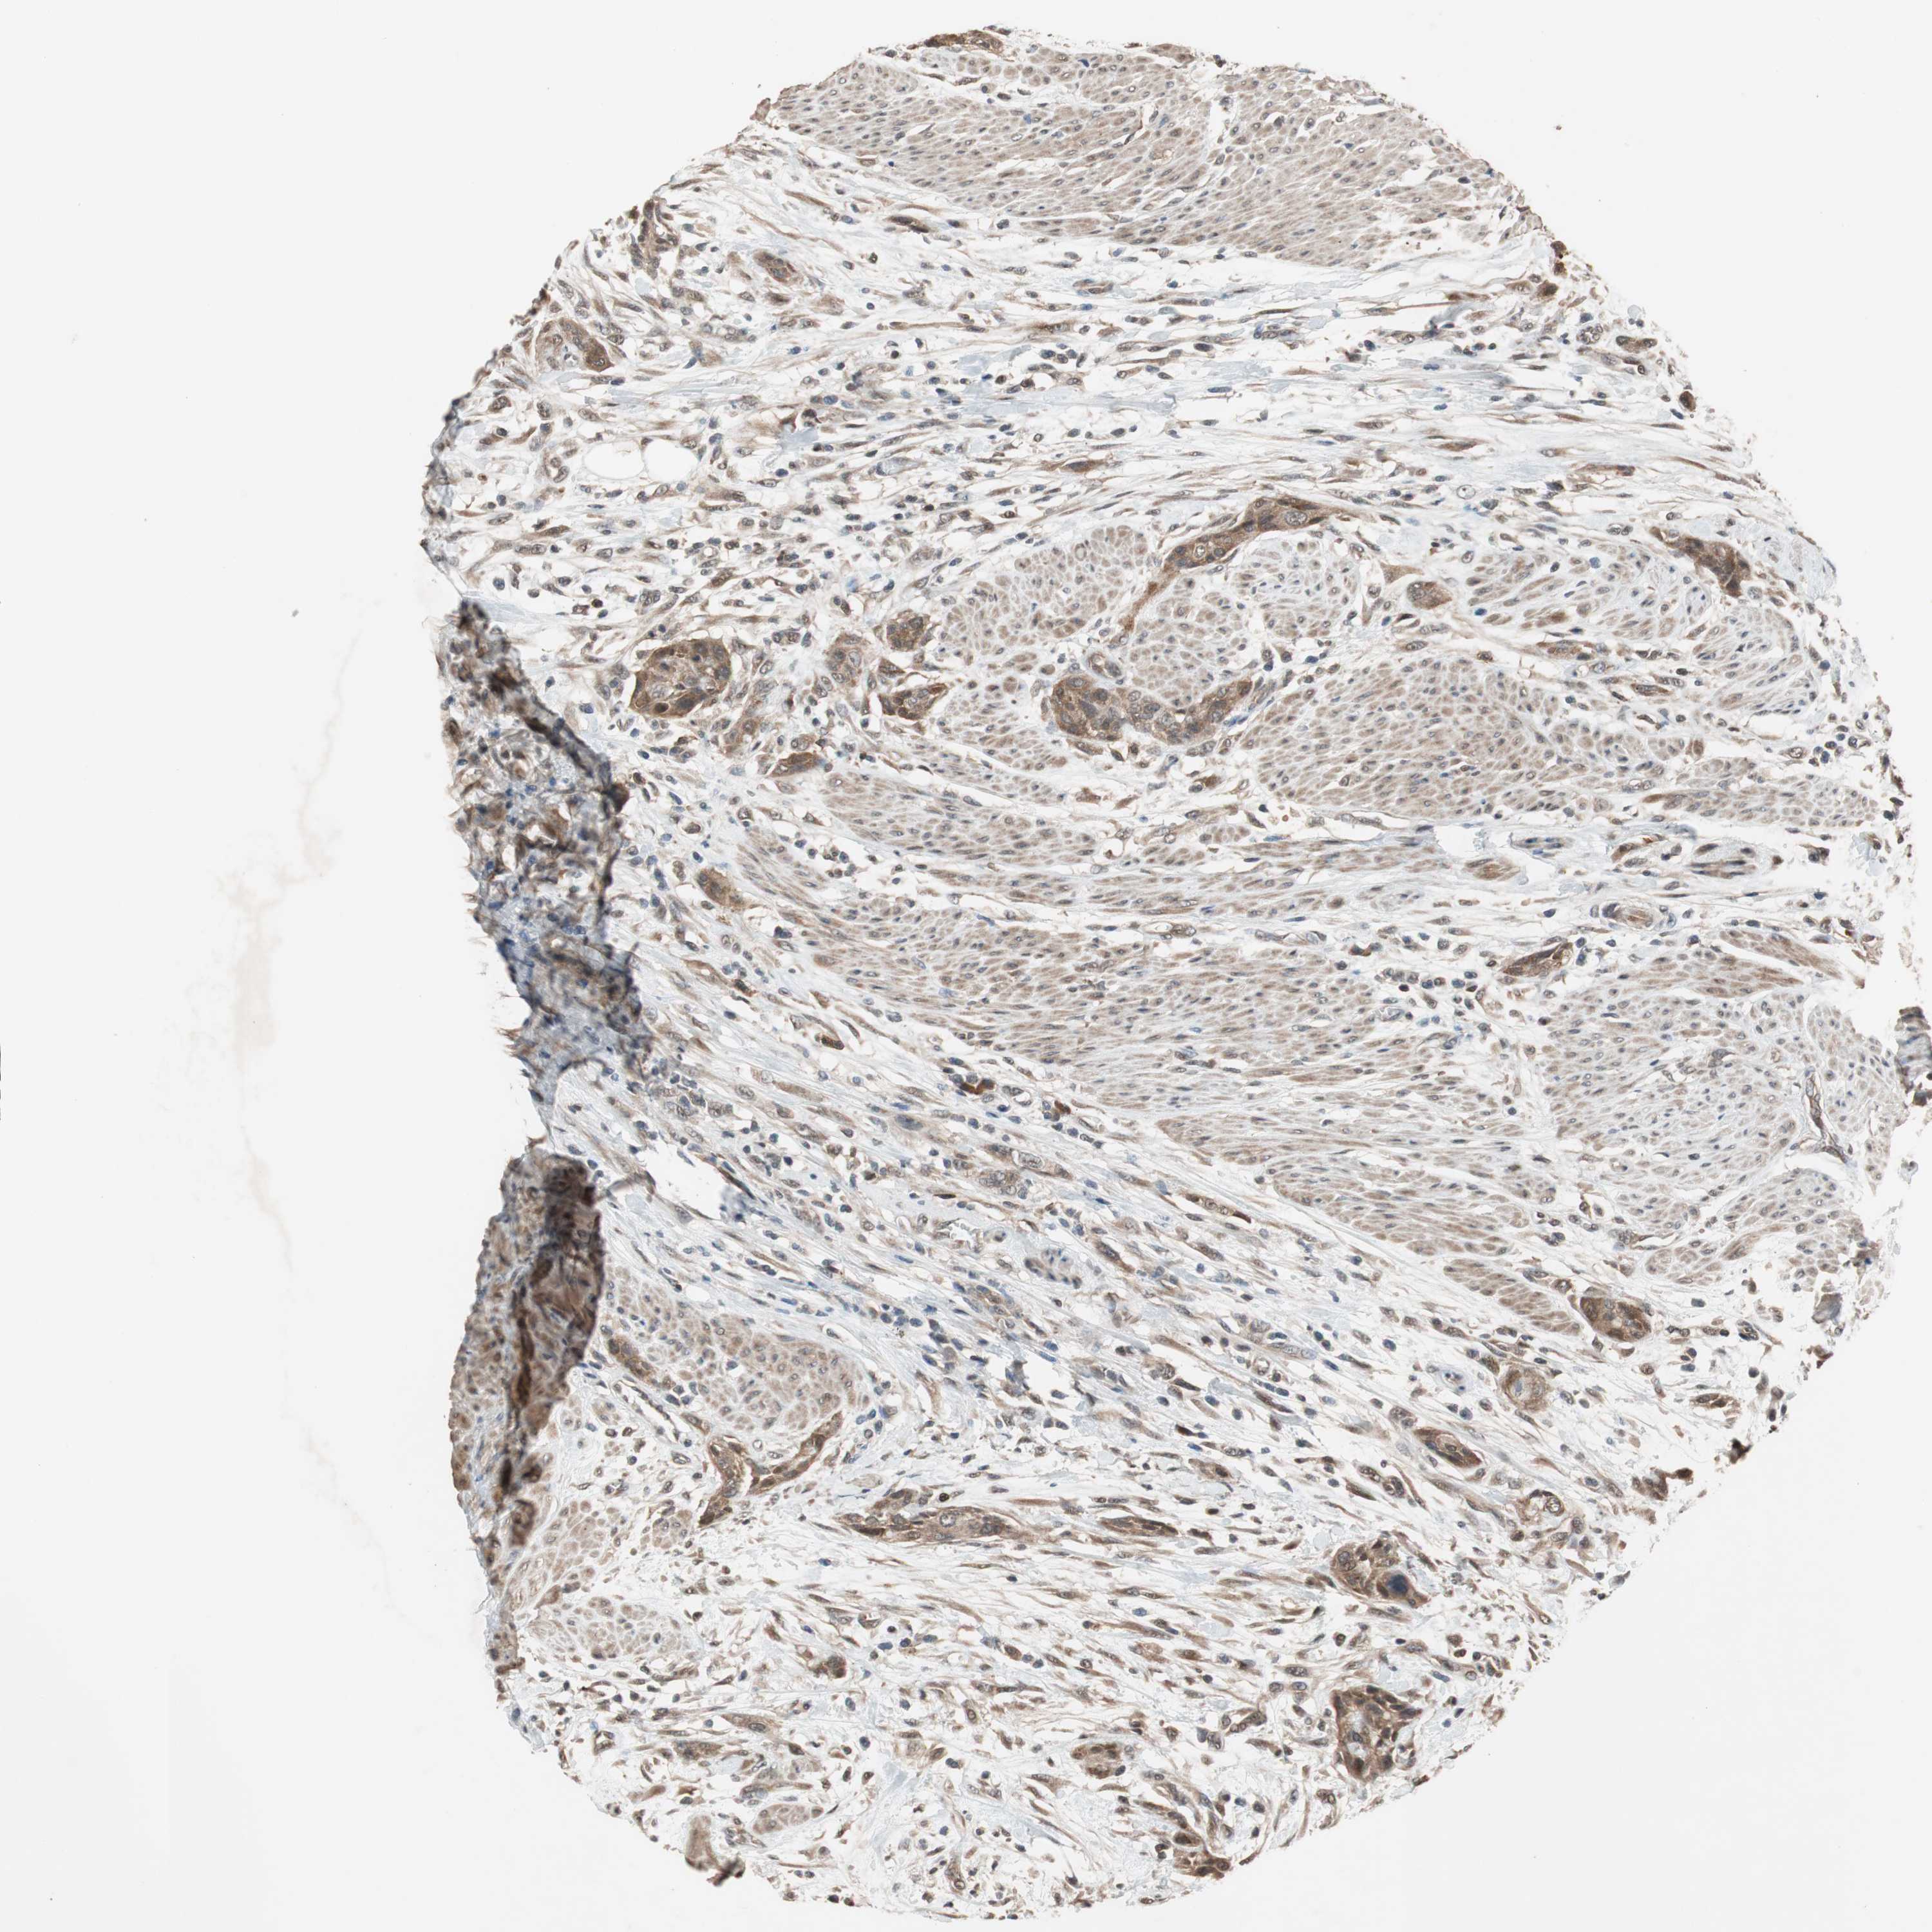

UROTHELIAL CANCER - Protein expressioni

A mouse-over function shows sample information and annotation data. Click on an image to view it in a full screen mode. Samples can be filtered based on level of antibody staining by selecting one or several of the following categories: high, medium, low and not detected. The assay and annotation is described here.

Note that samples used for immunohistochemistry by the Human Protein Atlas do not correspond to samples in the TCGA dataset.

Antibody stainingi

Antibody staining in the annotated cell types in the current human tissue is reported as not detected, low, medium, or high, based on conventional immunohistochemistry profiling in selected tissues. This score is based on the combination of the staining intensity and fraction of stained cells.

Each image is clickable and will lead to virtual microscopy that enables deeper exploration of all samples and also displays staining intensity scores, fraction scores and subcellular localization as well as patient and tissue information for each sample.

Antibody HPA009078

Staining

High

Medium

Low

Not detected

Intensity

Strong

Moderate

Weak

Negative

Quantity

>75%

75%-25%

<25%

None

Location

Nuclear

Cytoplasmic/membranous

Cytoplasmic/membranous,nuclear

Urothelial carcinoma, Low grade

Urothelial carcinoma, High grade